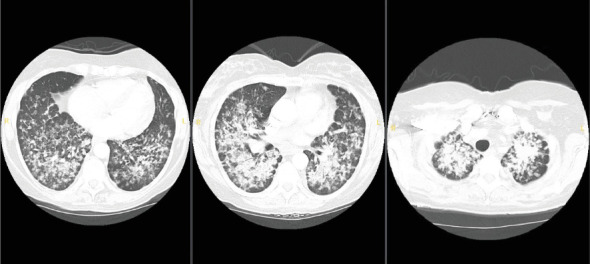

A 52-year-old female with a history of gastroesophageal reflux disease (GERD), hypertension (HTN), and supraventricular tachycardia (SVT) status postablation presented with progressive dyspnea and diffuse bilateral infiltrates on imaging. Symptoms began following exposure to a chicken farm, initially as a dry cough, evolving despite treatment with antibiotics, albuterol, and methylprednisolone. Emergency department CT imaging demonstrated bilateral linear, reticular, and nodular infiltrates. A negative infectious workup prompted bronchoscopy, confirming lung adenocarcinoma via immunohistochemical staining despite no significant smoking history, international travel, or other exposures. Brain MRI identified a solitary 7-mm enhancing lesion, guiding subsequent oncologic management. This case underscores the complexity of diagnosing atypical pulmonary symptoms and advocates for early bronchoscopic evaluation in suspected malignancies, particularly with pertinent family history.